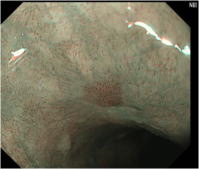

NBIシステムとは、粘膜表層の微細な血管を観察するシステムです。

内視鏡から特殊な波長の光を照射し粘膜の血管状態を観察することで、早期の咽頭癌、食道癌、胃癌、大腸癌など発見できる最新のシステムです。

415nmと540nmでは粘膜組織への伝播深度が互いに異なります。

このことが血管の走行状態の描写能力にさらなる効果を与えます。415nmの狭帯域光は粘膜表層の血管像を茶系の色調で、540nmの狭帯域光は表層下の血管像をシアン系の色調で描写します。この色の違いによって、血管の走行状態のより豊かな表現が可能となります。

狭帯域内視鏡システム(Narrow BandImaging; NBI) は観察照明光の狭小化を行うことにより、今までの内視鏡では見えなかった浅い粘膜部分の血管や粘膜の細かいところまでとらえることができるようになりました。

これだけではわかりづらいと思いますので簡単にいうと、早期のがんは粘膜構造が破壊され、腫瘍血管といって粘膜の浅いところに異常な血管を形成するので、これらの像をこのような内視鏡システムによって拾い上げます。